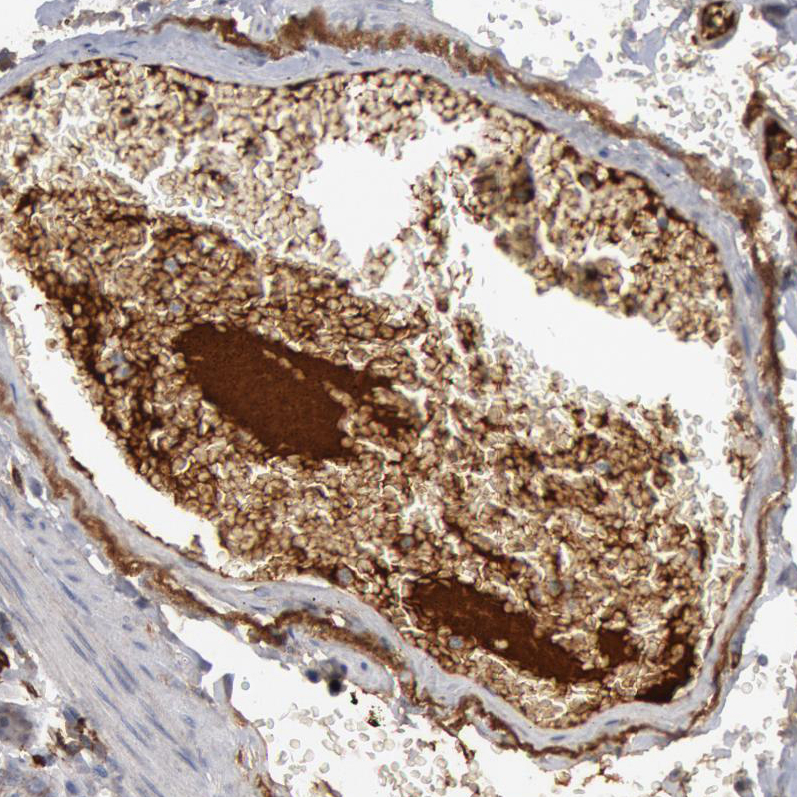

Immunohistochemical staining of human spleen shows strong cytoplasmic positivity in cells in red pulp.